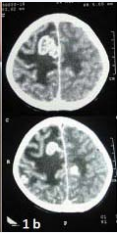

Investigations revealed anemia with normal leukocyte and platelet count and reactive Mantoux test (30×20mm). Two samples of gastric aspirate for AFB were negative. Renal and liver function tests and cerebrospinal fluid examination was normal. Contrast enhanced computed tomography (CECT) brain showed conglomerate ring enhancing lesions in right fronto-temporal and left parietal lobe suggestive of tuberculoma (Figure 1b).

CECT brain shows multiple conglomerated ring enhancing lesions in bilateral frontoparietal regions in parafalcine location with mild to moderate perilesional edema suggestive of tuberculomas.

Figure 1b: CECT brain shows multiple conglomerated ring enhancing lesions in bilateral frontoparietal regions in parafalcine location with mild to moderate perilesional edema suggestive of tuberculomas.

Skin biopsy revealed epitheloid cell granuloma with Langhans giant cells in papillary dermis; stain for AFB was negative. Biopsy findings were consistent with the diagnosis of lichen scrofulosorum.

Diagnosis of intracranial tuberculoma with lichen scrofulosorum was made and the child was started on four drugs ATT with steroid. Carbamazepine was added to control seizures. One month after initiation of therapy, skin lesions completely resolved without scarring.